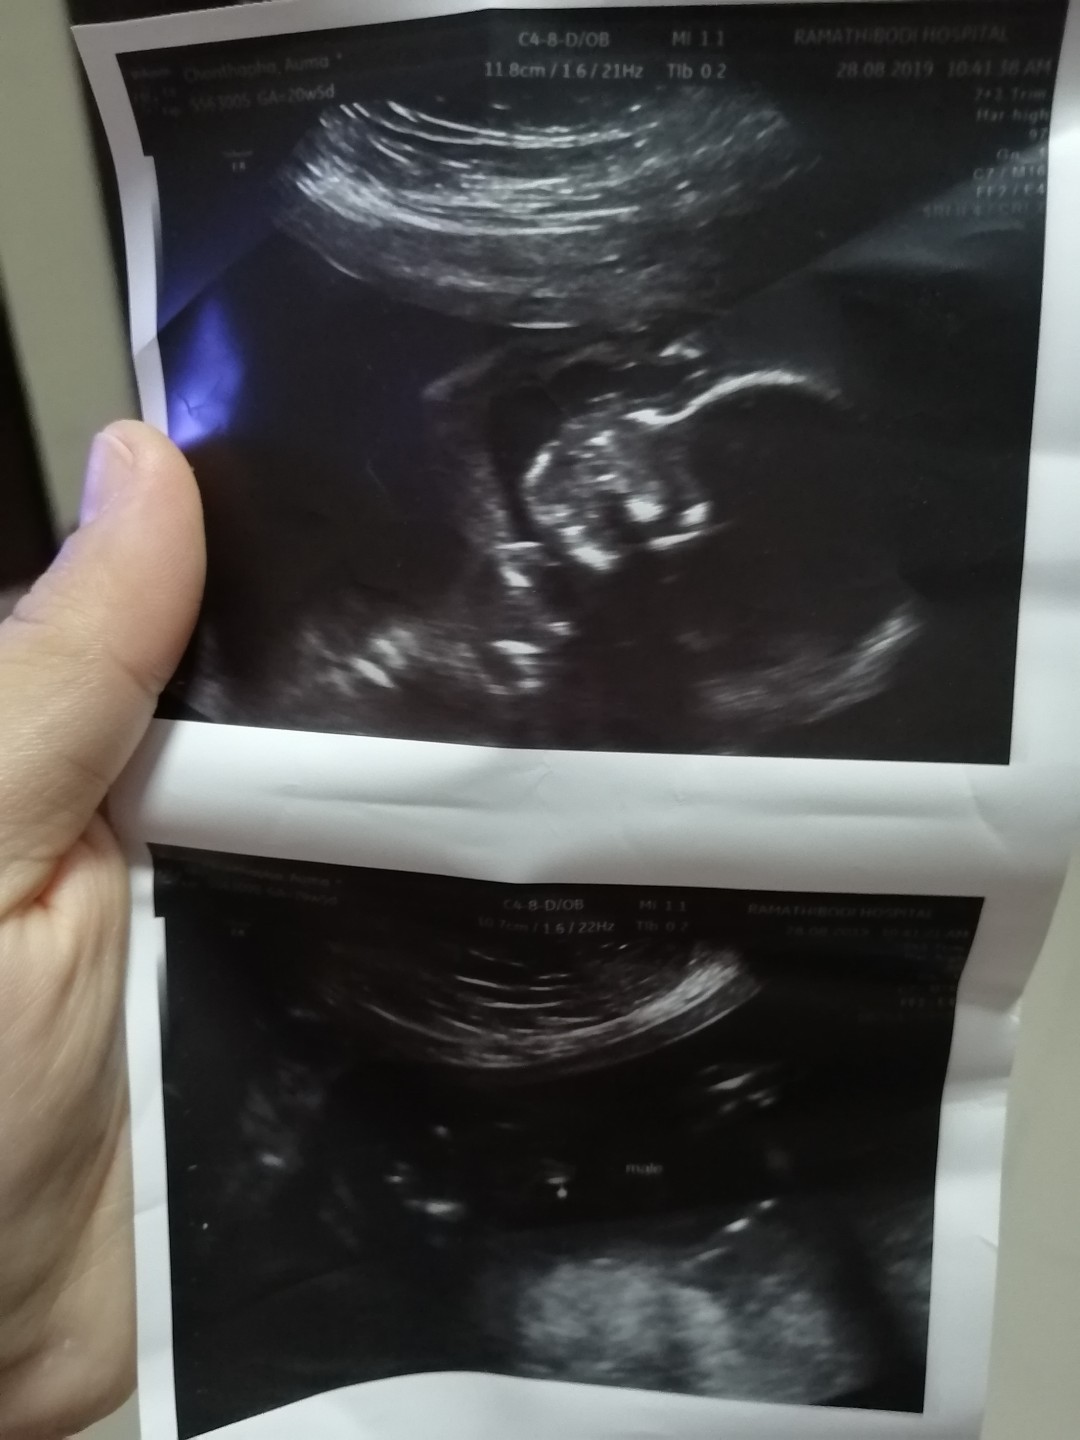

11สัปดาห์4วันค่า